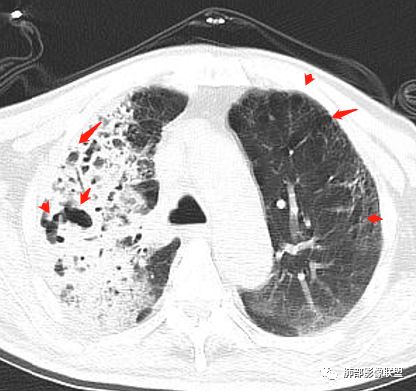

王秀仙:

右肺上叶大片实变,其内可见虫蚀样空洞及扩张支气管,其中一空洞内可见曲菌球样结构,右肺体积略缩小。老年糖尿病患者,慢阻肺背景,考虑右肺上叶干酪性肺炎并曲霉感染。

老年男性,糖尿病患者,右上肺大片实变,内可见多发虫蚀样空洞,右尖段近胸膜处一空洞内可见一类圆形结节影,支气管扩张,淋巴结肿大,双下肺索条,胸膜增厚。结合糖尿病病史,首选考虑结核干酪性肺炎合并曲霉菌感染,待排肺炎型肺癌

老年男性,糖尿病基础,有咳嗽,喘累症状,病程10天,右上肺大片实变,内虫嗜样,无壁空洞,支气管壁增厚,扩张,淋巴结肿大,胸膜增厚,考虑干酪性肺炎,鉴别粘液腺癌。

老年男性,糖尿病病史,慢性病程,右胸廓塌陷,右肺沿支气管分布实变及GGO,叶段分布趋势,其内见支气管充气征及虫蚀样空洞,周围间质受累,指向气道来源病变播散,纵隔淋巴结肿大,密度高伴钙化,综合考虑干酪性肺炎。鉴别肺炎型肺癌。

老年男性,有糖尿病史,右肺上叶大片实变影,有支气管充气征,支气管走行僵直,有扩张,有多发无壁小空洞和俩个稍大空洞,胸膜稍增厚,双下肺野间质性改变,考虑肺结核,干酪性肺炎可能性大。

老年男性,右肺上叶大片实变,边界局部清楚,局部模糊,其内见支气管充气征及多发大小不等的小泡状及分枝状无壁空洞。双肺下叶磨玻璃样间质性改变。综合考虑右肺上叶结核,干酪性肺炎可能。

支气管、内部的小囊腔,部分无壁小空洞,病灶部分边界偏清,支持结核

1、结核干酪空洞常很干净,很彻底,而粘液腺癌空洞内有液性成份,不干净。

2、支气管:干酪样肺炎内的支气管破坏的,扩张的,粘液腺癌小支气管多狭窄的堵塞的,大支气管较完好,枯枝征。

6、结核灶周围磨玻璃少见,粘液腺癌磨玻璃影清楚。结核灶常有收缩,钙化,树丫等等。很重要,粘液腺癌分布弥漫,远处飘散的边界清楚的磨玻璃结节影有重要诊断意义。

7、形态,结核收缩,粘液腺癌局部膨胀,叶间裂有时候是膨胀下坠的。